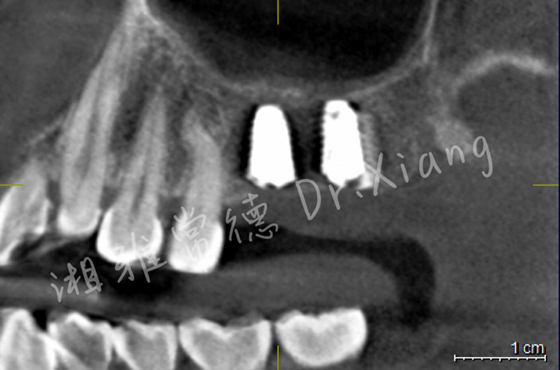

经过9个月骨愈合后,患者复查锥形束CT,骨愈合十分满意。9月中旬,向峰医师种植团队成功为患者实施了第二步的手术,取出内固定装置的同时为患者成功微创的植入2枚种植体,完成了患者左上颌区域的软硬组织的自然恢复和改建。

接下来,患者即将进入治疗的“最终章”。3个月后取模,完成种植牙冠的修复,重建缺失的牙齿。

种植体精准微创植入